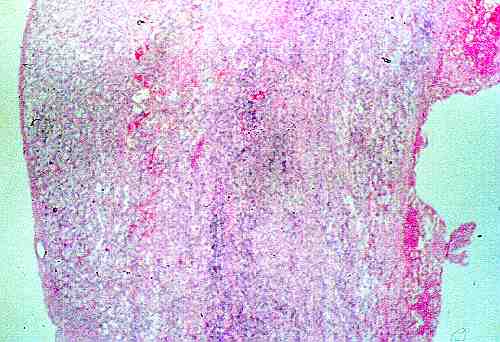

Figura 3: Caso 1. La neoformación esta constituida por una pared de tejido fibroso, con presencia de calcificaciones.